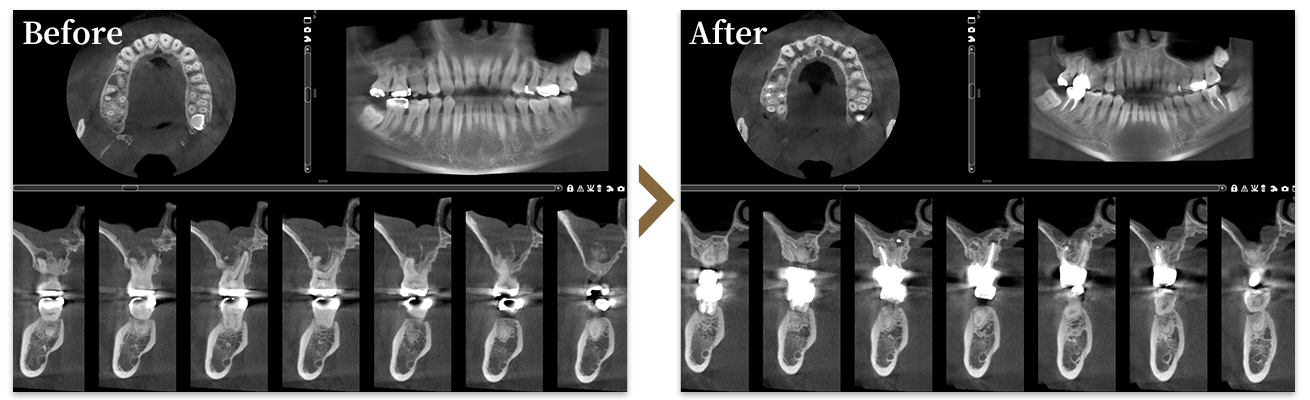

主訴 歯牙破折・歯根嚢胞

(根管治療専門医にて抜歯を勧められるも、非抜歯を希望の為当院受診)

治療内容 根管治療(補綴物:ジルコニアクラウン)

治療期間・回数 2023年12月25日~2024年2月14日(来院回数9回)

治療費(自費) 339,000円(税抜)